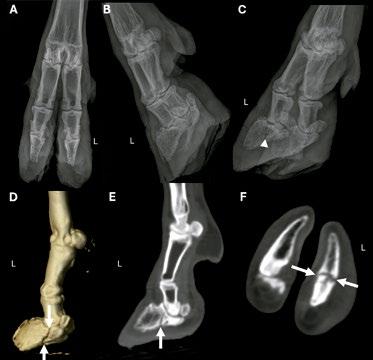

En los tres casos de TC de extremidades distales, se identificaron lesiones como artritis séptica asociada a osteomielitis de la articulación metacarpofalángica y del metacarpo distal (Imagen 3), así como una fractura no desplazada de la tercera falange en una pezuña anterior (Imagen 4).

Imagen 4. Radiografías (A-C), imagen de TC en estación con renderizado volumétrico tridimensional en plano sagital (D) e imágenes de TC en estación (E y F) obtenidas con un algoritmo óseo de alta frecuencia en ventana ósea (WW/ WL, 1.500/300) de la articulación metacarpofalángica izquierda (L) y la pezuña de un macho caprino castrado de 7 años con cojera crónica del miembro torácico izquierdo. La letra L indica los aspectos dorsal y lateral de la extremidad. En la revisión inicial no se identificaron alteraciones en las radiografías dorsopalmar (A), laterolateral (B) y oblicua lateral (C). La reconstrucción tridimensional con renderizado volumétrico en plano sagital (D), la reconstrucción multiplanar sagital (E) de la pezuña lateral y la imagen transversal de TC de los dígitos distales (F) revelaron una fractura articular crónica no desplazada de la tercera falange de la pezuña lateral (flechas). Tras la reevaluación de las radiografías después de la TC, se identificó en esta localización una línea radiolúcida incompleta y mal definida en la radiografía oblicua lateral (C; cabeza de flecha blanca).